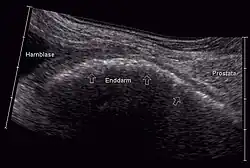

Sonographisch werden insbesondere Restharn- und Prostatavolumen beurteilt. Die Sonographie ermöglicht auch die Erkennung eines (meist urodynamisch besonders relevanten) vergrößerten Mittellappens. Die Ultraschalluntersuchung wird meist transrektal ausgeführt, ermöglicht aber auch transabdominal eine gute Bestimmung des Restharnvolumens und bei voller Blase auch von Prostatavolumen, endovesikalem Mittellappen und der Anhebung der Blase durch das BPH (intravesikale prostatische Protrusion).[21] Die erhobenen Befunde werden zur Beurteilung des Progressionsrisikos und der Notwendigkeit einer Behandlung verwendet. Eine pathologisch erhöhte Restharnmenge alleine ist nicht beweisend für eine den Harnfluss behindernde BPH. Mittels Sonographie des oberen Harntraktes kann eine relevante Harnstauung ausgeschlossen werden. Sogenannte bildgebende Verfahren wie Computertomografie (CT), Magnetresonanztomografie (MRT) oder Ausscheidungsurografie sind zur Diagnose einer BPH nicht angezeigt.[22] Die Durchführung eines Urogramms ist bei Verdacht auf eine Erkrankung der Nieren angezeigt.